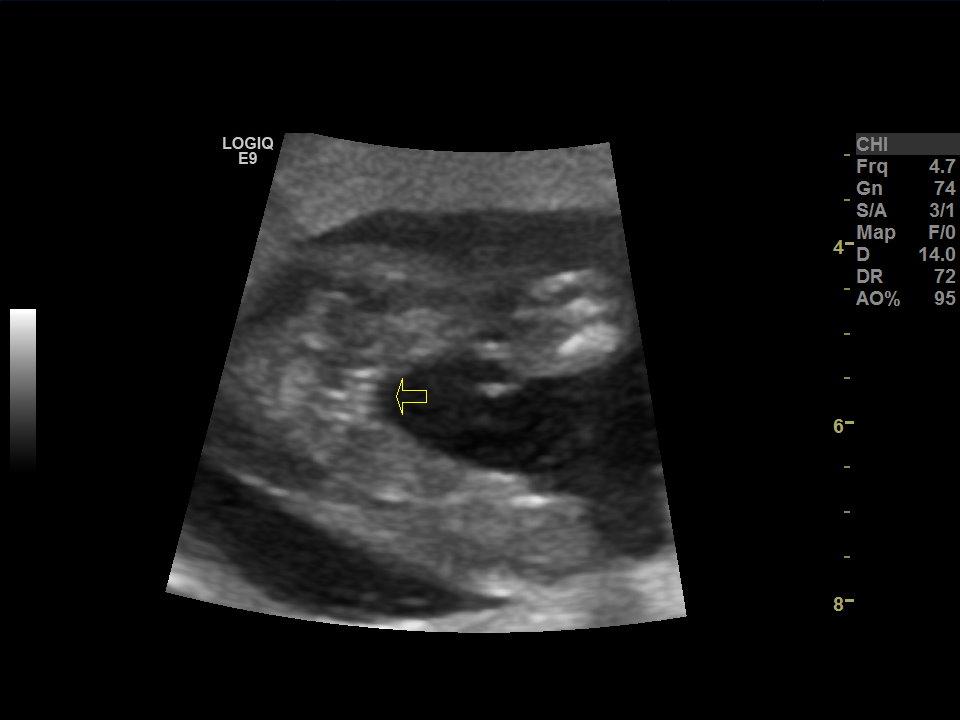

I posted my ultrasound pics from my 12 week 4 day scan previously and I just got back from my 18 week 1 day paid Gender Scan :)

Attachment 39018